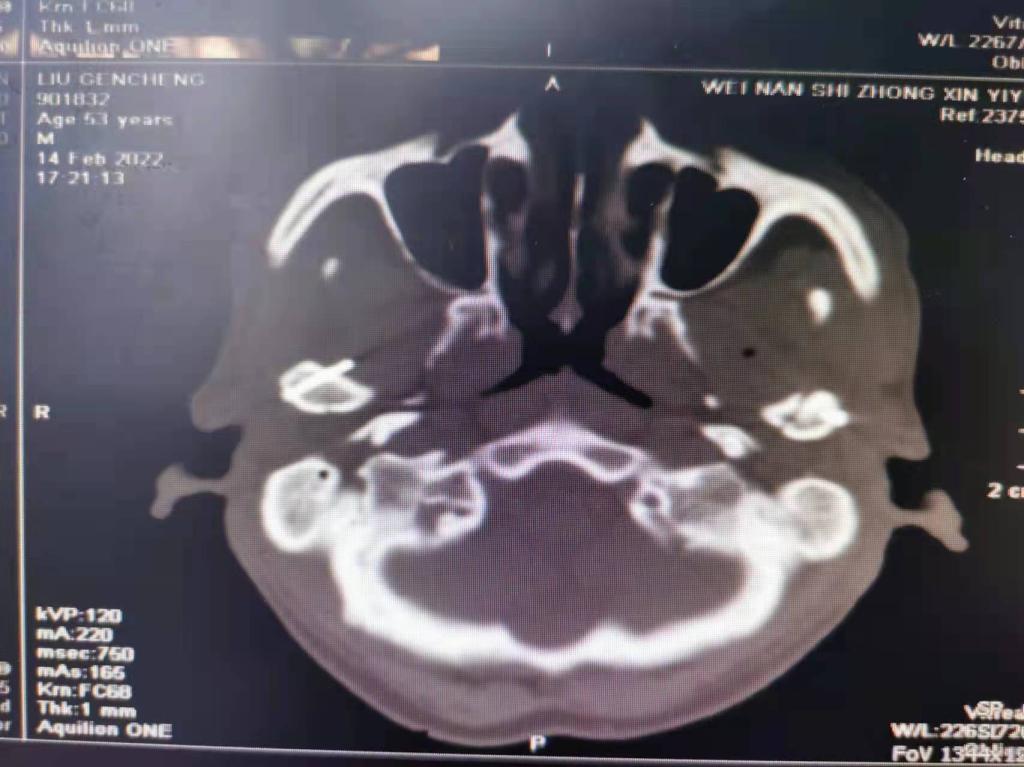

据了解,53岁的患者刘先生在1月25日当天走路不慎摔倒致下颌损伤,造成颏部软组织裂伤和张口困难,前往当地卫生院进行颏部裂伤清创缝合术。术后辗转到MILAN.COM口腔科门诊就诊,并进行颌面部CT检查提示为下颌颏部正中和双侧髁状突骨折,双侧下颌升支高度不一致,右侧较左侧变短1cm,张口重度困难,咬合关系错乱。刘先生因考虑在春节过后再入院治疗,于2月8日再次前来口腔科以“下颌骨骨折”收治人院。

口腔科主治医师蔺非非为患者入院后进行完善术前常规检查和颌间牵引恢复咬合关系。科主任李瑞春结合患者实际病情和检查结果认为,患者的髁突骨折在下颌骨骨折中所占比例较高,约为17.0%-36.3%。髁突骨折时,耳前区有明显的疼痛,局部肿胀、压痛。通过手指深入外耳道或在髁突部触诊,如张口时髁突运动消失,可能有骨折段移位。双侧低位骨折时,2个髁突均被翼外肌拉向前内方,双侧下颌支被拉向上方,可出现后牙早接触,前牙开秴。髁状突骨折易引起下颌后缩,张口困难,咬合关系错乱,关节强直等并发症。考虑患者系陈旧性骨折应尽早实施手术,避免骨折导致的张口困难、关节强直等并发症。因患者已经错过最佳治疗时期,决定尽快为患者进行手术治疗。

科主任李瑞春和主治医师蔺非非经过缜密的术前讨论和充分评估,手术在全身麻醉下进行,术中克服术野狭小操作不便困难,将下颌骨骨折完好对位,顺利地完成了"双侧髁状突和下颌颏部正中骨折切开复位内固定术"。术后检查患者面部对称,双侧下颌升支高度一致,咬合关系已恢复。